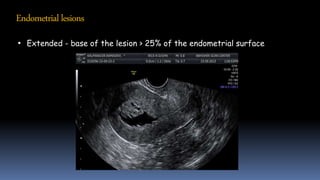

Endometriallesions

• Extended - base of the lesion > 25% of the endometrial surface

Endometriallesions • Extended -base of the lesion > 25% of the endometrial surface